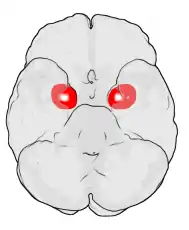

Dorsal view of the amygdalae in an average human brain

Frontal view of the amygdalae in an average human brain